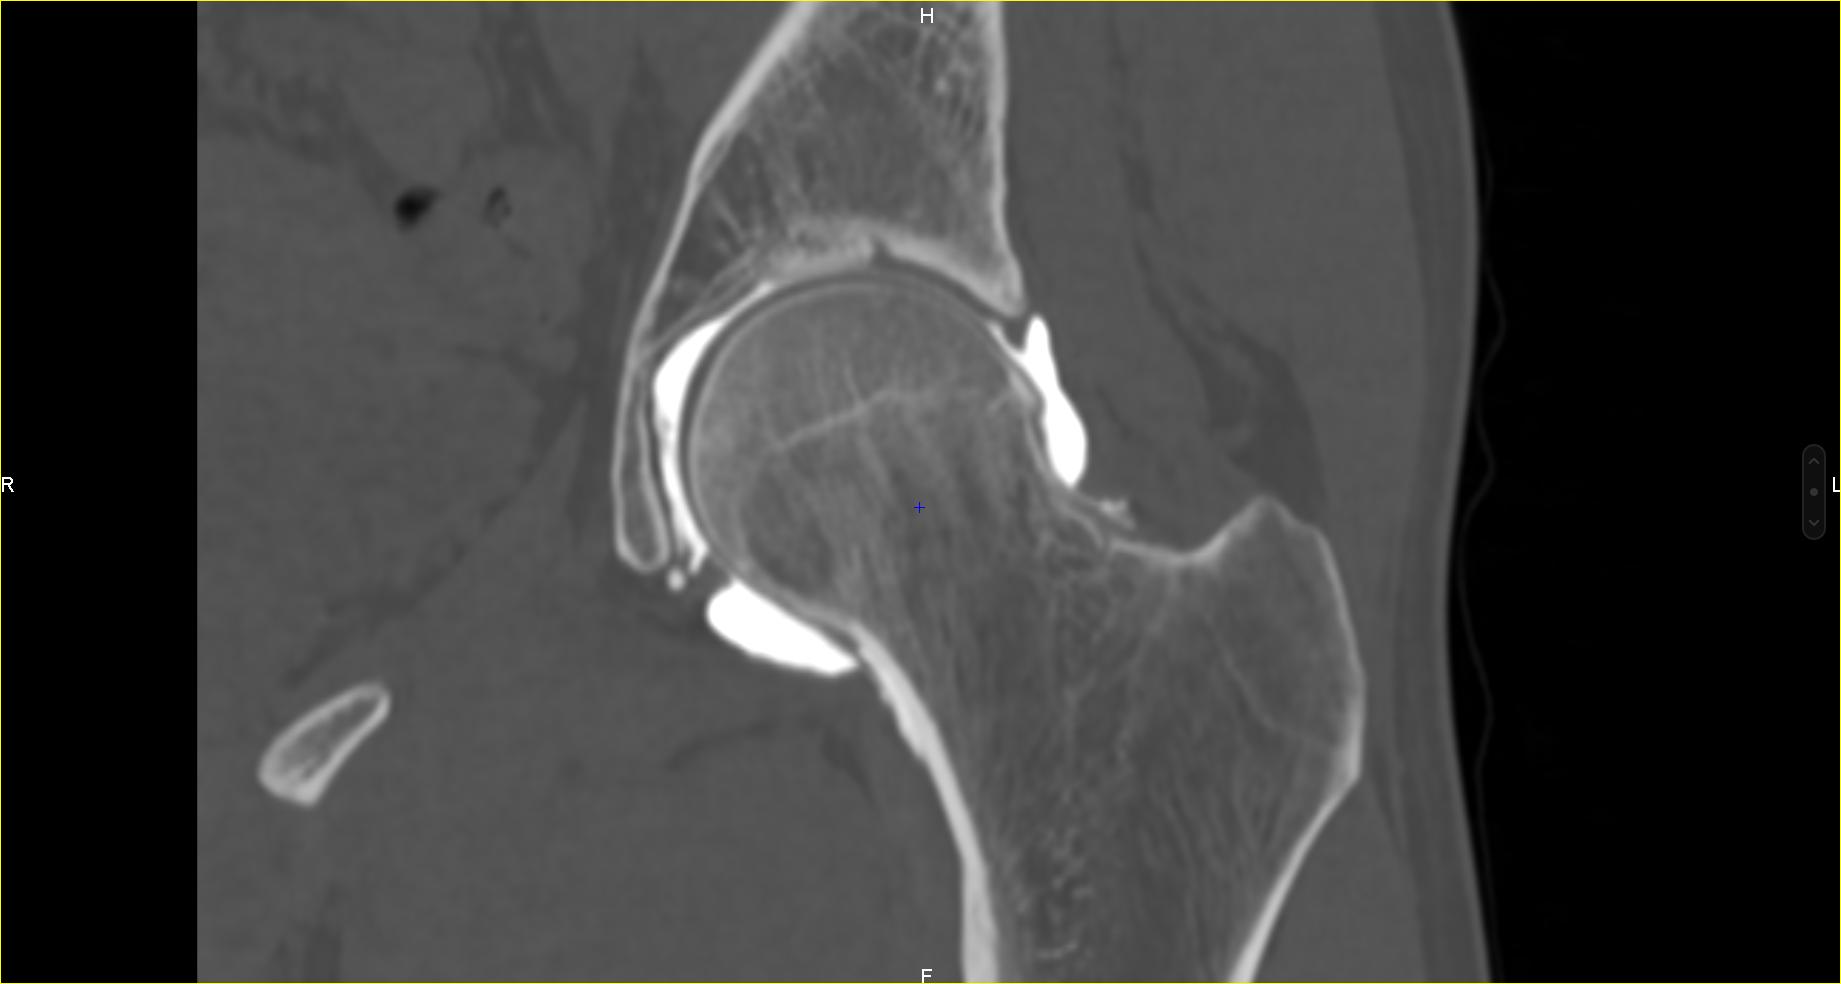

Scanner et arthroscanner

L’arthroscanner est un examen utilisant les rayons X, il permet d’étudier finement toutes les structures d’une articulation. Il s’agit d’un examen diagnostique invasif composé de deux parties :

- une injection d’un produit de contraste au sein de l’articulation d’intérêt, réalisé en condition stérile sous guidage radiographique. Le patient est alors invité à faire quelques mouvements pour que le produit diffuse dans toute l’articulation.

- la réalisation du scanner à proprement parler permettant d’analyser les différentes structures de l’articulation : cartilage (revêtement de la surface osseuse), les ligaments, les os, les tendons ou encore la membrane synoviale (membrane tapissant l’intérieur d’une cavité articulaire et sécrétant le liquide synovial).